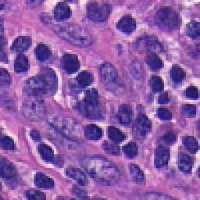

Medical Diagnostics & Research: Researchers and healthcare providers can use LDANN-BASIC to assist in the identification of lymphocyte classes, helping to diagnose diseases like leukemia or lymphoma more efficiently and enhancing our understanding of the immune system.

Pharmaceutical Development & Drug Testing: The model can be employed in pharmaceutical labs to study the effects of new drugs on lymphocyte populations, contributing to the development of more effective medications or therapies targeting specific immune conditions.

Automated Clinical Laboratory Systems: LDANN-BASIC can be integrated into automated image analysis workflows within clinical laboratories, streamlining the process of analyzing patient samples and reducing the risk of human error in lymphocyte classification.

Educational Purposes: The model can serve as a teaching tool for medical students, clinical laboratory scientists, and immunology researchers to learn and visually understand different types of lymphocytes, thereby improving their skills and knowledge in the field of histology and pathology.

Remote and Telemedicine Diagnostics: LDANN-BASIC can be used in remote healthcare settings or telemedical diagnostic systems, enabling healthcare professionals to analyze blood samples from patients even if they are located in rural or remote areas with limited access to specialized labs.